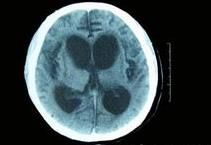

昏迷狀態長達6年之久的植物人大腦兩半球極度嚴重的損害或功能障礙所造成的自覺的思維活動能力的喪失,但間腦與腦幹的功能有充裕的保留,因此一些自主神經反射與運動反射都有保存,並可有正常的睡眠-覺醒周期.

在若干種瀰漫性腦損傷後可以出現暫時性的植物人狀態(vegetative state).持續超過4周以上的植物人狀態被人為地稱為持久的植物人狀態.持久的植物人狀態最常發生在嚴重的腦外傷或全面性缺氧(例如由於心臟停搏)之後,恢復意識的預後較差.

一旦植物人狀態持續超過數月,很少見有好轉,無人能完全恢復.處於持久植物人狀態中的成年人,大約有50%的機會能在頭部受傷後開始的6個月內重新恢復一定程度的意識對環境能有所反應.通常會發生永久性的腦功能障礙.過了半年以後,愈來愈少的病人能對周圍環境有任何系統性的感知.在醫院中發生心臟停搏後出現植物人狀態的病例中,只有10%~15%能恢復意識,在醫院外發生心臟停搏者能恢復意識的不超過5%.在腦外傷後處於持久植物人狀態的兒童中,大約60%在1年之內能恢復意識,但缺氧性腦損害的兒童病例的預後則與成人病例大致相同.只有極小一部分病例能在6個月以後有相當程度的意識恢復以致可以獨立照顧自己.